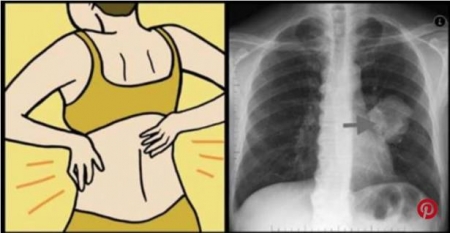

إذا ظهرت عليكم هذه الأعراض فأنتم مصابون بمرض خبيث .. احذروا!